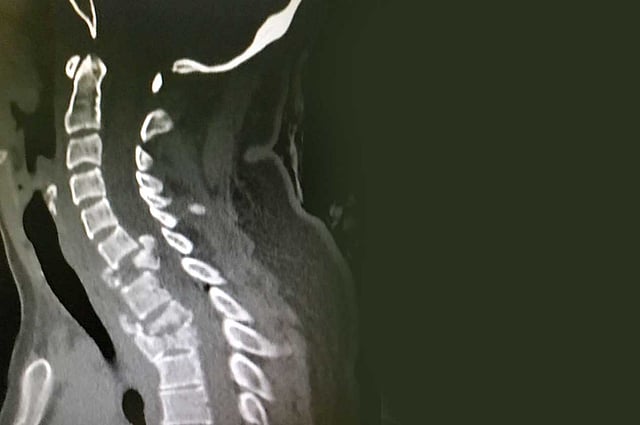

وذكر بيانٌ صادرٌ عن «صحة القصيم» اطلعت عليه «عاجل»، أن الحادث الذي تعرضت له الشابة (26 عامًا) أصابها كذلك بضعف الحركة في الأطراف العلوية ووجود «رض» بالنخاع الشوكي الرقبي، وكسر مفتت بالفقرة الرقبية السابعة، وكسر مستقر بالفقرتين الظهريتين الثانية والثالثة.

وفور وصول المريضة إلى قسم الطوارئ، باشر أطباء الطوارئ وأطباء الجراحة بقيادة استشاري جراحة المخ والأعصاب الدكتور عبدالله السويري حالة المصابة، وتم إجراء الفحوصات الطبية وعمل الأشعة اللازمة.

وقرر الأطباء، بحسب البيان، وضع المريضة على الشد الرقبي لمدة ثلاثة أيام؛ حيث كان هناك انغماس رئوي أيسر، وبعد أن استقرت الحالة تم نقلها إلى غرفة العمليات، وأجريت لها عملية استئصال الفقرة السابعة كاملة، ووضع بدلًا منها ما يسمى  بـ«ميش» مع طعم عظمي وصفيحة وبراغي بين الفقرات، وإزالة كامل الضغط عن النخاع الشوكي الرقبي.